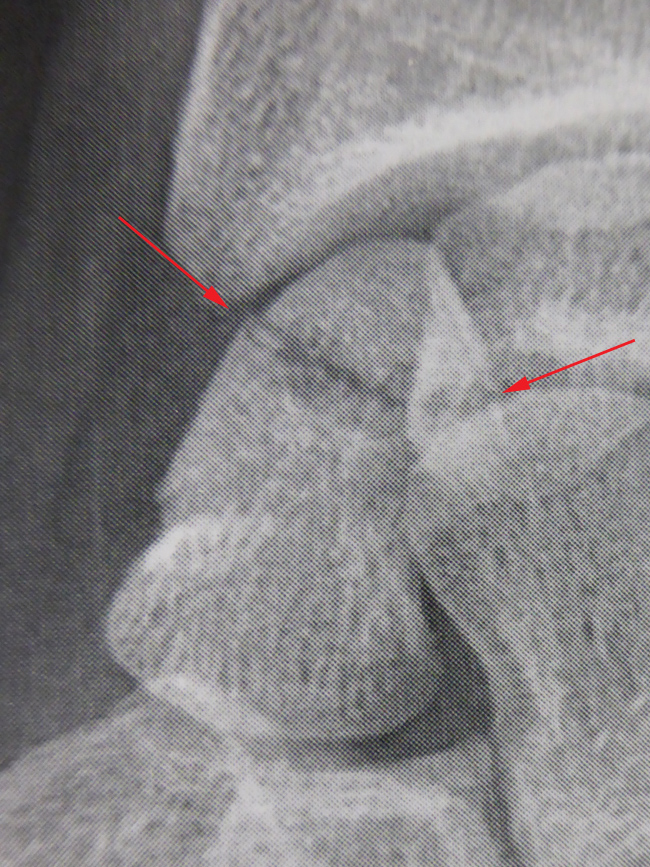

Il est indispensable de faire des radiographies. Si la douleur persiste après plusieurs jours et même si les radiographies sont normales, un scanner est indispensable pour diagnostiquer la fracture et préciser si la fracture est déplacée ou non.

Fractures déplacées du corps du scaphoïde

Ces fractures doivent replacées en position anatomique, c’est ce qu’on appelle la « réduction » de la fracture. Il s’agit toujours d’une intervention chirurgicale. La qualité de la réduction peut s’effectuer par contrôle radiologique, sous arthroscopie ou à l’œil nu après ouverture de l’articulation.